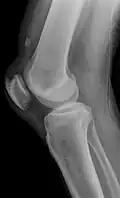

![]() | |

| An x-ray demonstrating quadriceps tendon rupture. Note the abnormal angle of the patella and soft-tissue swelling marked by the arrow. | |